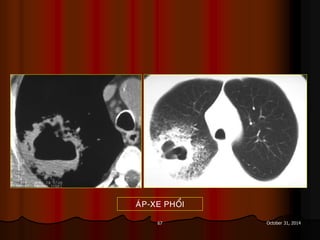

NHÖÕNG BOÙNG DAÏNG HANG

AÙP-XE PHOÅI